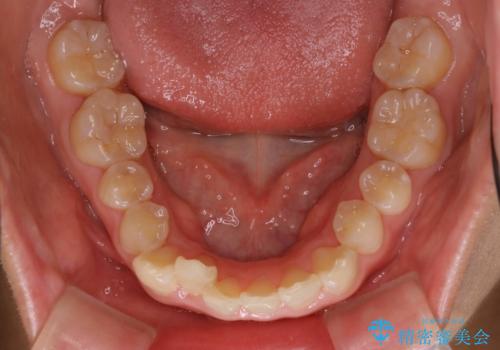

ハーフリンガル矯正 抜歯をして前歯を下げる

- 上顎の両側第1小臼歯抜歯による抜歯矯正を計画した。

上顎の抜歯により上の前歯の位置を大幅に後ろに下げることができます。

奥歯の位置関係など、様々な要素を加味し、適応を判断する必要があります。